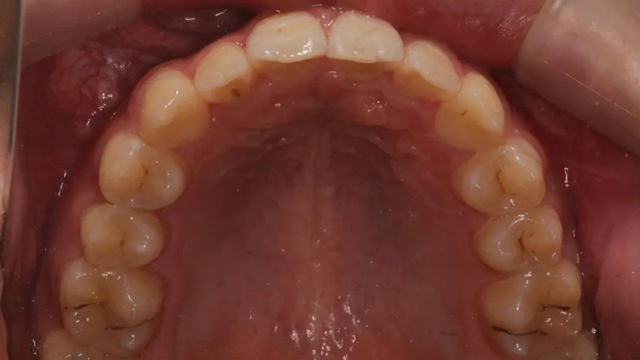

2024年9月(矫正结束后口内照)

“隐形矫正一般2-3月复诊一次,从节约时间来说很受家长青睐,但前提是小朋友要有很好的依从性,这是获得满意效果的前提。案例中的这个小朋友和家长与医生的配合度非常高,这也是我们能治疗成功的必要因素。”

该病例的治疗周期长达三年,跨替牙期和年轻恒牙期。治疗结束时,小患者收获了一口整齐美观的牙齿,也从满脸稚气的孩童长成了青葱少年。